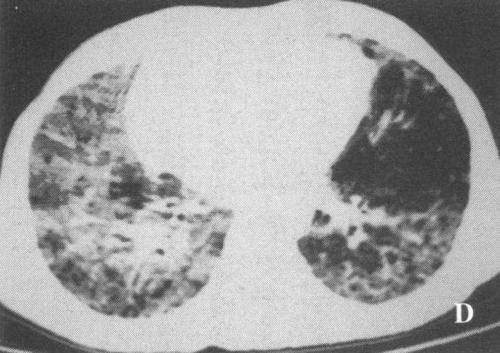

3、干燥综合征肺脏损害

肺脏是干燥综合征最容易损伤的内脏器官,有的患者会以肺部症状首先发病,出现咽喉干痛、声音嘶哑,反复干咳、气道粘液不易咳出,活动后胸闷气喘,这样的病人往往去呼吸科就诊。所以女性如有不明原因干咳、气促,活动后气短、发绀等表现时,应警惕干燥综合征肺脏受累。肺部一旦受损,最终会发展为肺间质纤维化,常因感染危及生命。